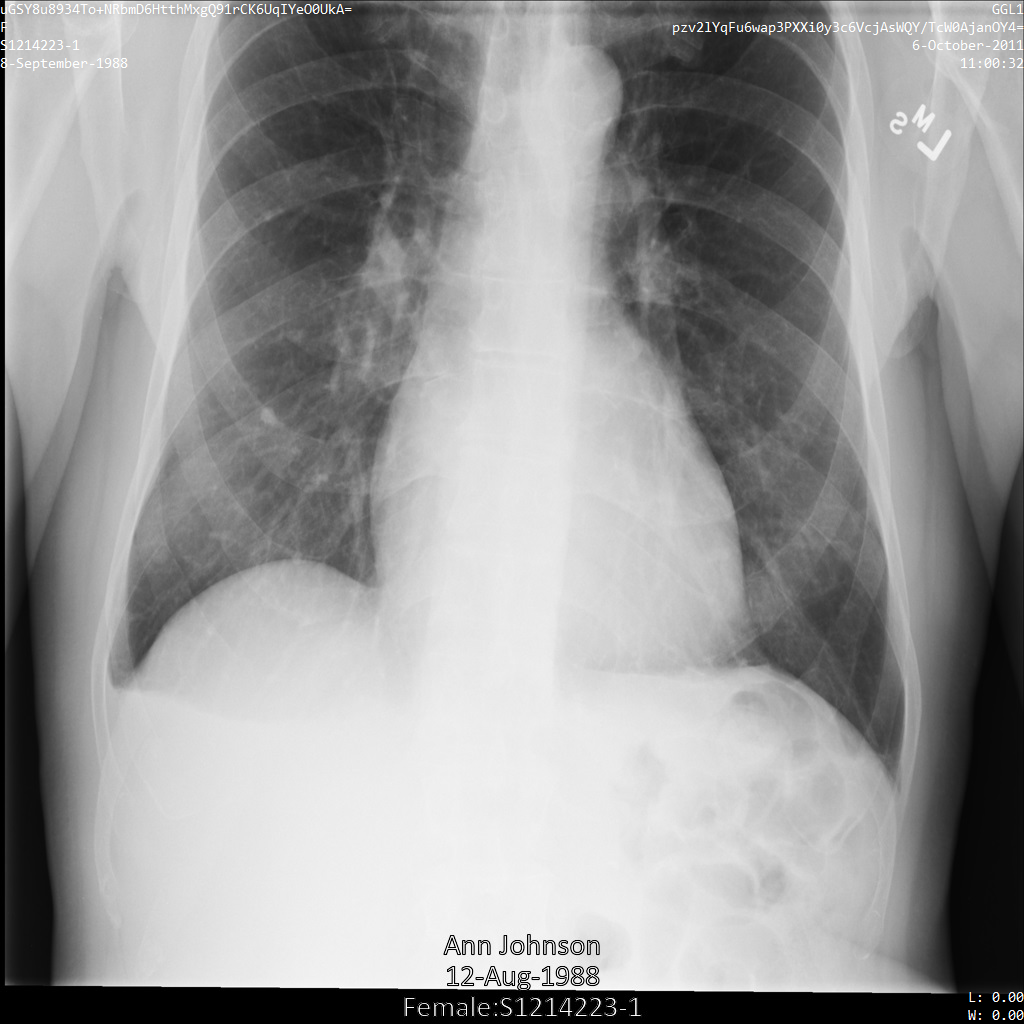

Después de enviar la imagen a la API de Cloud Healthcare mediante las opciones REDACT_ALL_TEXT y DEIDENTIFY_TAG_CONTENTS, la imagen aparece de la siguiente manera. Observa los siguientes cambios:

- Los nombres en la esquina superior izquierda y en la esquina superior derecha de la imagen se transformaron con una

CryptoHashConfig - Las fechas en la esquina superior izquierda y derecha de la imagen se transformaron con un

DateShiftConfig - Se oculta el texto grabado que aparece en la parte inferior de la imagen.